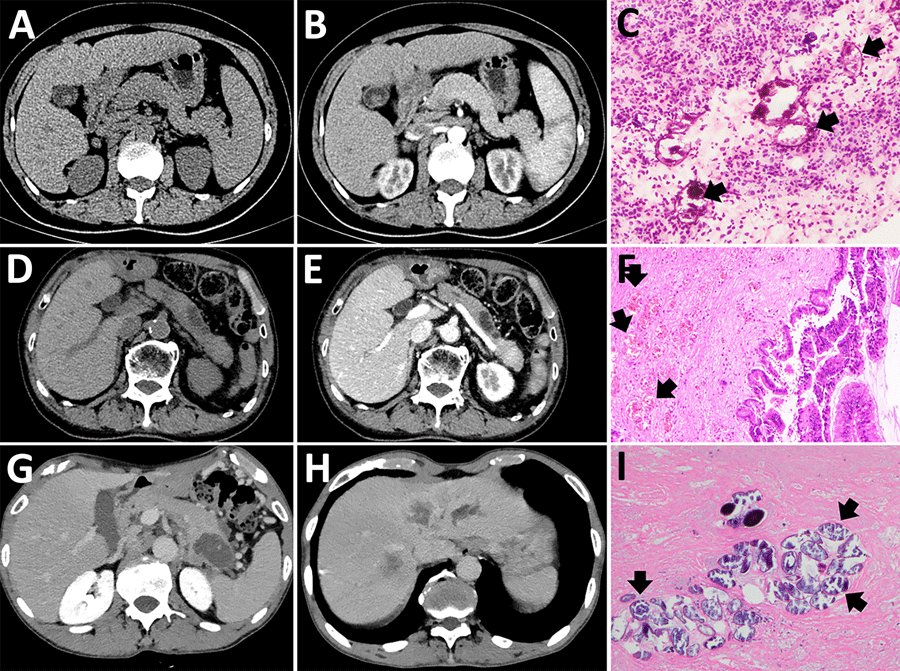

Figure 1. Imaging from 4 cases of pancreatic schistosomiasis, China, 2020–2024. A, B) Computed tomography (CT) images from patient 1 revealing a mass involving the pancreas. C) Pathologic examination from fine-needle aspiration of patient 1 showing fibrinous exudate and schistosome eggs (arrows). D, E) Abdominal CT of patient 2 showing a nonenhancing, tubular lesion adjacent to the main pancreatic duct in the body of the pancreas. F) Pathologic examination of sample from patient 2 showing intraductal papillary mucinous neoplasm with moderate dysplasia and scattered schistosome eggs (arrows). G, H) Abdominal CT of patient 3 revealing a low-density mass in the pancreatic tail and multiple ring-enhancing hepatic nodules. I) Pathologic examination of sample from patient 3 showing schistosome egg deposition (arrows) with associated tissue necrosis.